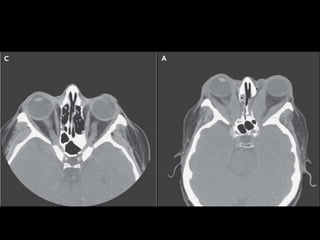

Clasificación de las alteraciones oculares en la Enf de Graves según la AAT

Clase                                  Definición

0                     No hay síntomas ni signos

1                     Solamente signos

2                     Afectación de partes

blandas

3                     Proptosis mayor a 22 mm

4                     Músculos extrínsecos

afectados

5                     Córnea afectada

6                     Pérdida de la visión

Clasificación de lasalteraciones oculares en la Enf de Graves según la AAT Clase Definición 0 No hay síntomas ni signos 1 Solamente signos 2 Afectación de partes blandas 3 Proptosis mayor a 22 mm 4 Músculos extrínsecos afectados 5 Córnea afectada 6 Pérdida de la visión